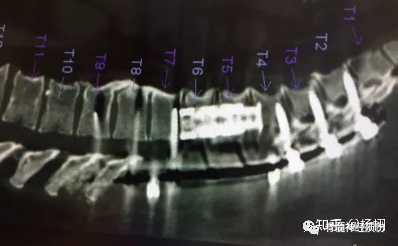

低头玩手机时间久了就会导致各种颈椎病,就说说很常见的颈椎变直,不仅会压迫到神经,还会严重影响气质,让整个人变得猥琐。 对于颈椎类的疾病,希望能帮助你了解它,并改善它。 健康的颈椎都具有向前弯曲的c型曲线。但生活中长期的不良姿势,却十分容易导致颈椎出现骨性畸形